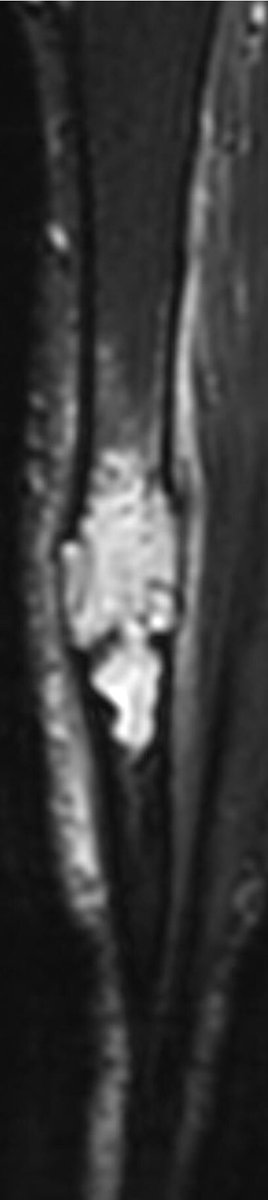

MRI is mandatory for accurate local staging (intramedullary extent, multifocal tibial and fibular disease and extra-osseous extension) and surgical planning. AD is typically isointense / mildly hyperintense to muscle on T1 weighted images

similar to fat on fast spin-echo T2 and hyperintense on inversion recovery and fluid-sensitive fat saturated sequences. The tumour enhances intensely and homogeneously.

The tumour in the current case appeared to have arisen in the anterior cortex, extending inferiorly into both cortex and medulla, as a single focus of disease. The trabeculated appearance on radiographs appears to reflect the unusual extension of tumour through tibial cortex.

, with preservation of vertical ridges of cortical bone, surrounded by tumour, adjacent to areas of marked cortical thinning. Oedema-like hyperintensity on the bone surface suggests imminent fracture